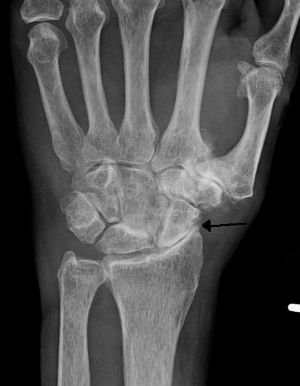

View On GoogleThe Risk of Shoulder Osteoarthritis Should Not Be Discounted Either...